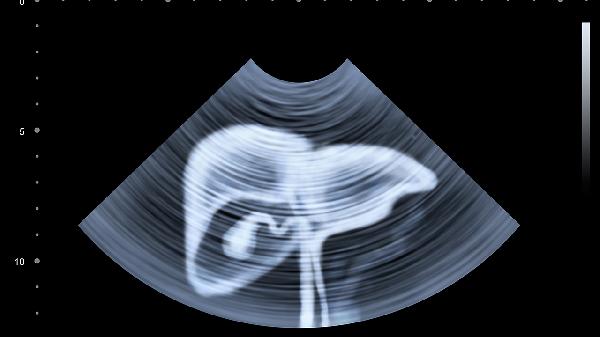

某些疾病如子宫内膜异位症、肠系膜脂膜炎等主要表现为组织密度改变而非占位病变。需结合超声造影、腹腔镜等检查明确,妇科疾病建议联合阴道超声评估。